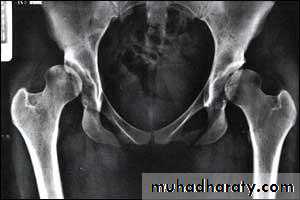

Imaging1. U/S in the neonatal period. Should done for every child at risk and every hip with sign of instability2. X-ray signs In neonate → Von rosens line In infancy → Shentons line Perkins line Acetabular roof angle Smal epiphysis In child hood → false acetabulum3. Arthrography